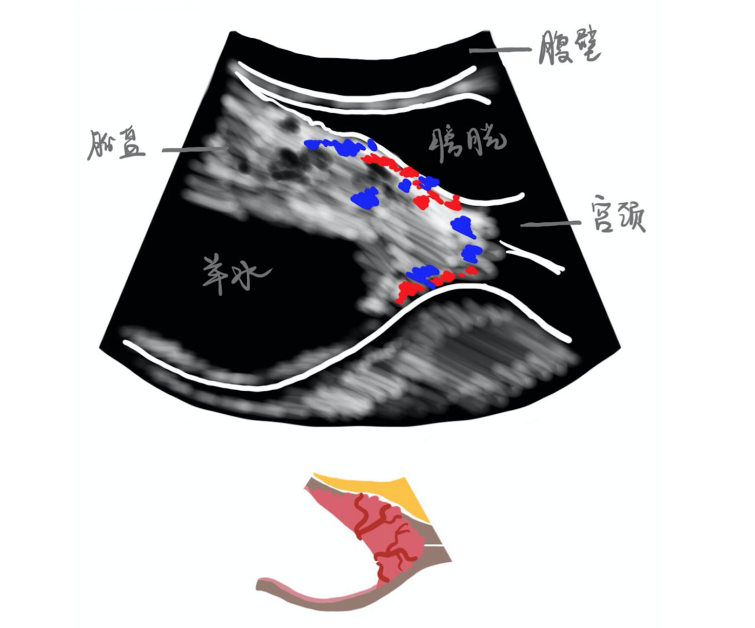

媽媽們?cè)谡麄€(gè)孕期都會(huì)做許多次超聲檢查,來(lái)觀察寶寶的生長(zhǎng)發(fā)育和判斷胎盤的形態(tài)位置。那么“胎盤植入”,這個(gè)讓諸多有剖宮產(chǎn)史的媽媽所擔(dān)憂的話題,在孕期超聲中又有什么特殊的表現(xiàn)呢?拿起手中的超聲報(bào)告,我們一起來(lái)看看。 胎盤腔隙: 又被成為“胎盤陷窩”或“胎盤血竇”,是胎盤中異常擴(kuò)張的血管所形成的,超聲報(bào)告圖片中表現(xiàn)為白色的胎盤中有邊界不規(guī)則的深色斑塊。 胎盤后低回聲區(qū): 胎盤部位正常的層次依次為胎盤、蛻膜(低回聲-黑灰色)和子宮肌層(高回聲-灰白色),所以胎盤后方的低回聲區(qū)消失就意味著胎盤已經(jīng)侵襲到了肌層。 子宮-膀胱界面回聲異常: 子宮與膀胱之前隔有一層漿膜組織,如果界面回聲中斷或不均勻,有可能是胎盤生長(zhǎng)侵襲到漿膜或膀胱的表現(xiàn)。 胎盤位置: 如果出現(xiàn)“前置胎盤”則表示胎盤生長(zhǎng)的位置較低,接近子宮頸內(nèi)口。隨著孕周的增加,部分位置較低的胎盤可隨著子宮的生長(zhǎng)變成正常位置的胎盤,但有剖宮產(chǎn)史的媽媽們?nèi)圆豢纱笠?,需要通過(guò)超聲密切監(jiān)測(cè)。 宮頸形態(tài)、宮頸血竇: 可以反映出胎盤的生長(zhǎng)是否侵襲到了宮頸。 子宮肌層厚度: 子宮肌層越薄,胎盤生長(zhǎng)穿透肌層的風(fēng)險(xiǎn)越大,子宮也越容易發(fā)生破裂。一般子宮肌層小于1mm則發(fā)生子宮破裂的風(fēng)險(xiǎn)較高,媽媽們更需注意。 超聲多普勒: 超聲多普勒可以觀察到血流的豐富程度,紅色的血流是流向探頭的血流,藍(lán)色的血流是背向探頭的血流。 1.胎盤基底部血流:胎盤基底部血流豐富,意味著血管已經(jīng)生長(zhǎng)到了胎盤與肌層的交界面。 2.子宮肌層-膀胱壁高度血管化:有這種表現(xiàn)的媽媽發(fā)生穿透性胎盤植入的概率比較大,因?yàn)檠芤呀?jīng)突破漿膜層,到達(dá)了子宮肌層與膀胱之間的界面上,甚至侵及膀胱。 因此,懷疑為胎盤植入的媽媽們非常需要有經(jīng)驗(yàn)的超聲大夫進(jìn)行充分的評(píng)估、轉(zhuǎn)診到有胎盤植入診治經(jīng)驗(yàn)的醫(yī)院、準(zhǔn)確判斷胎盤植入的程度、制定個(gè)性化的治療方案。 北京大學(xué)第一醫(yī)院胎盤植入團(tuán)隊(duì)分析了2000多例胎盤植入的孕婦,將上述超聲表現(xiàn)與流產(chǎn)、剖宮產(chǎn)等危險(xiǎn)因素相結(jié)合,設(shè)計(jì)了胎盤植入評(píng)分來(lái)評(píng)估媽媽的植入程度和寶寶的預(yù)后,為母兒保駕護(hù)航。 關(guān)于胎盤植入,媽媽們還有哪些想要了解的內(nèi)容?我們會(huì)在評(píng)論區(qū)選擇高贊的問(wèn)題在下一期回答。我們下周再見(jiàn)! 作者:楊馨蕊 楊慧霞